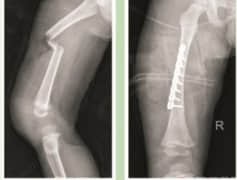

• 骨折案例分享

骨折案例分享

骨折如果治疗不当会造成畸形愈合、骨不连等后果,专业治疗和精心的术后辅导,对于预后非常重要。骨折治疗要过三关,首先是手术关,然后是术后感染关,第三关是骨折愈合与功能恢复关。广东药科大学广州复星禅诚医院骨科能良好处理第一、二关,手术均达到高质复位,没有意外感染,